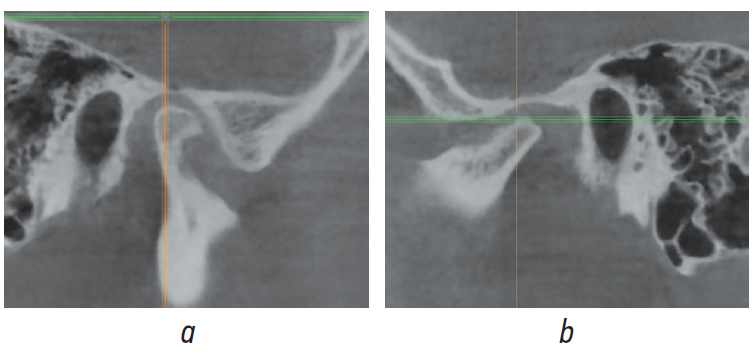

Обоим пациентам предложен аппаратурно-хирургический план лечения, подразумевающий санацию полости рта, декомпенсацию соотношения зубных рядов при помощи брекет-системы, двучелюстную/одночелюстную операцию с перемещением обеих челюстей/нижней челюсти вперед. Анализ КЛКТ височно-нижнечелюстного сустава (ВНЧС) пациента Ч. (рис. 8 а, b) позволил рассматривать в качестве альтернативного плана коррекцию соотношения зубных рядов в сагиттальном и вертикальном направлениях при помощи аппарата Гербста [2–4]. Анализ КЛКТ ВНЧС пациентки Ж. (рис. 9 а, b) выявил переднее положение головки нижней челюсти справа и ее резорбцию слева, что позволило обосновать план лечения с применением ортогнатической операции и эндопротезированием с целью коррекции признаков ЗЧЛА в сагиттальном, вертикальном и трансверзальном направлениях [5] (рис. 10).

Рис. 9. Сагиттальный срез конусно-лучевой компьютерной томографии височно-нижнечелюстного сустава пациентки Ж. справа (а) и слева (b)

Fig. 9. Sagittal slice of cone-beam computed tomography of the temporomandibular joint of patient Zh.; right (a) and left (b)